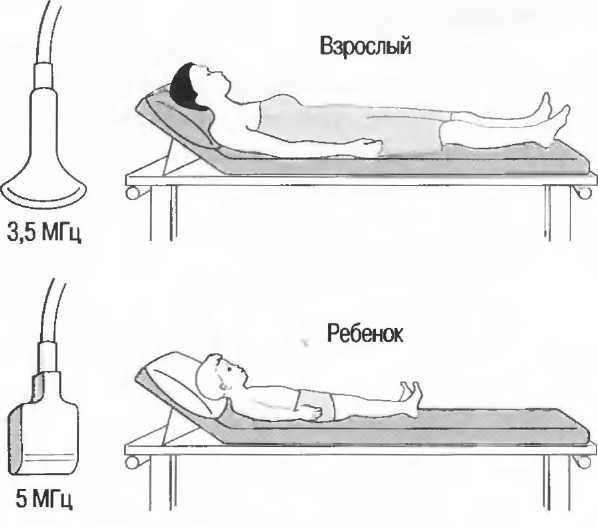

Затухание

Ткани тела поглощают и рассеивают ультразвук по-разному. Высокие частоты поглощаются и рассеиваются (гасятся) в большей степени, чем низкие. Поэтому, чтобы достичь более глубоких тканей, необходимо использовать более низкие частоты, так как менее вероятно, что эти волны затеряются при прохонодении через ткани. На практике оптимально использовать частоту около 3,5 МГц для глубокого сканирования у взрослых и частоту 5 МГц и выше для исследования более худых пациентов или детей. Частота 5 МГц и выше используется для исследования поверхностных органов у взрослых.

Высокие частоты дают более детальное изображение, но имеют меньшую проникающую способность.

Выбор соответствующего датчика

Наилучшим датчиком для общей практики является конвексный датчик с частотой 3,5 МГц с фокусировкой на расстоянии 7-9 см. Если такого датчика нет, необходимо наличие линейного секторного датчика с частотой 3,5 МГц. При необходимости исследования детей и худых взрослых желательно дополнить набор датчиком с частотой 5 МГц с фокусировкой 5-7 см.

1. Ультразвуковые исследования в акушерстве. Для общих исследований в акушерстве используется линейный или конвексный датчик с частотой 3,5 или 5 МГц с глубиной фокусировки на 7-9 см. Если закупается только один датчик, выбирайте датчик с частотой 3,5 МГц. Датчик с частотой 5 МГц предпочтителен на ранних сроках беременности. В поздние сроки беременности лучше использовать датчик с частотой 3,5 МГц.

2. Ультразвуковые исследования в общей практике. Если проводятся исследования в верхней части живота и таза у взрослых, в том числе и акушерские исследования, предпочтительнее выбор секторного или конвексного датчиков с частотой 3,5 МГц с глубиной фокусировки на 7-9 см.

3. Ультразвуковые исследования в педиатрии. Для детей необходим датчик с частотой 5 МГц с глубиной фокусировки на 5-7 см. При исследовании мозга новорожденного используется секторный датчик с частотой 7,5 МГц с глубиной фокусировки на 4-5 см (этот датчик также используется для исследования яичек и структур шеи у взрослых).